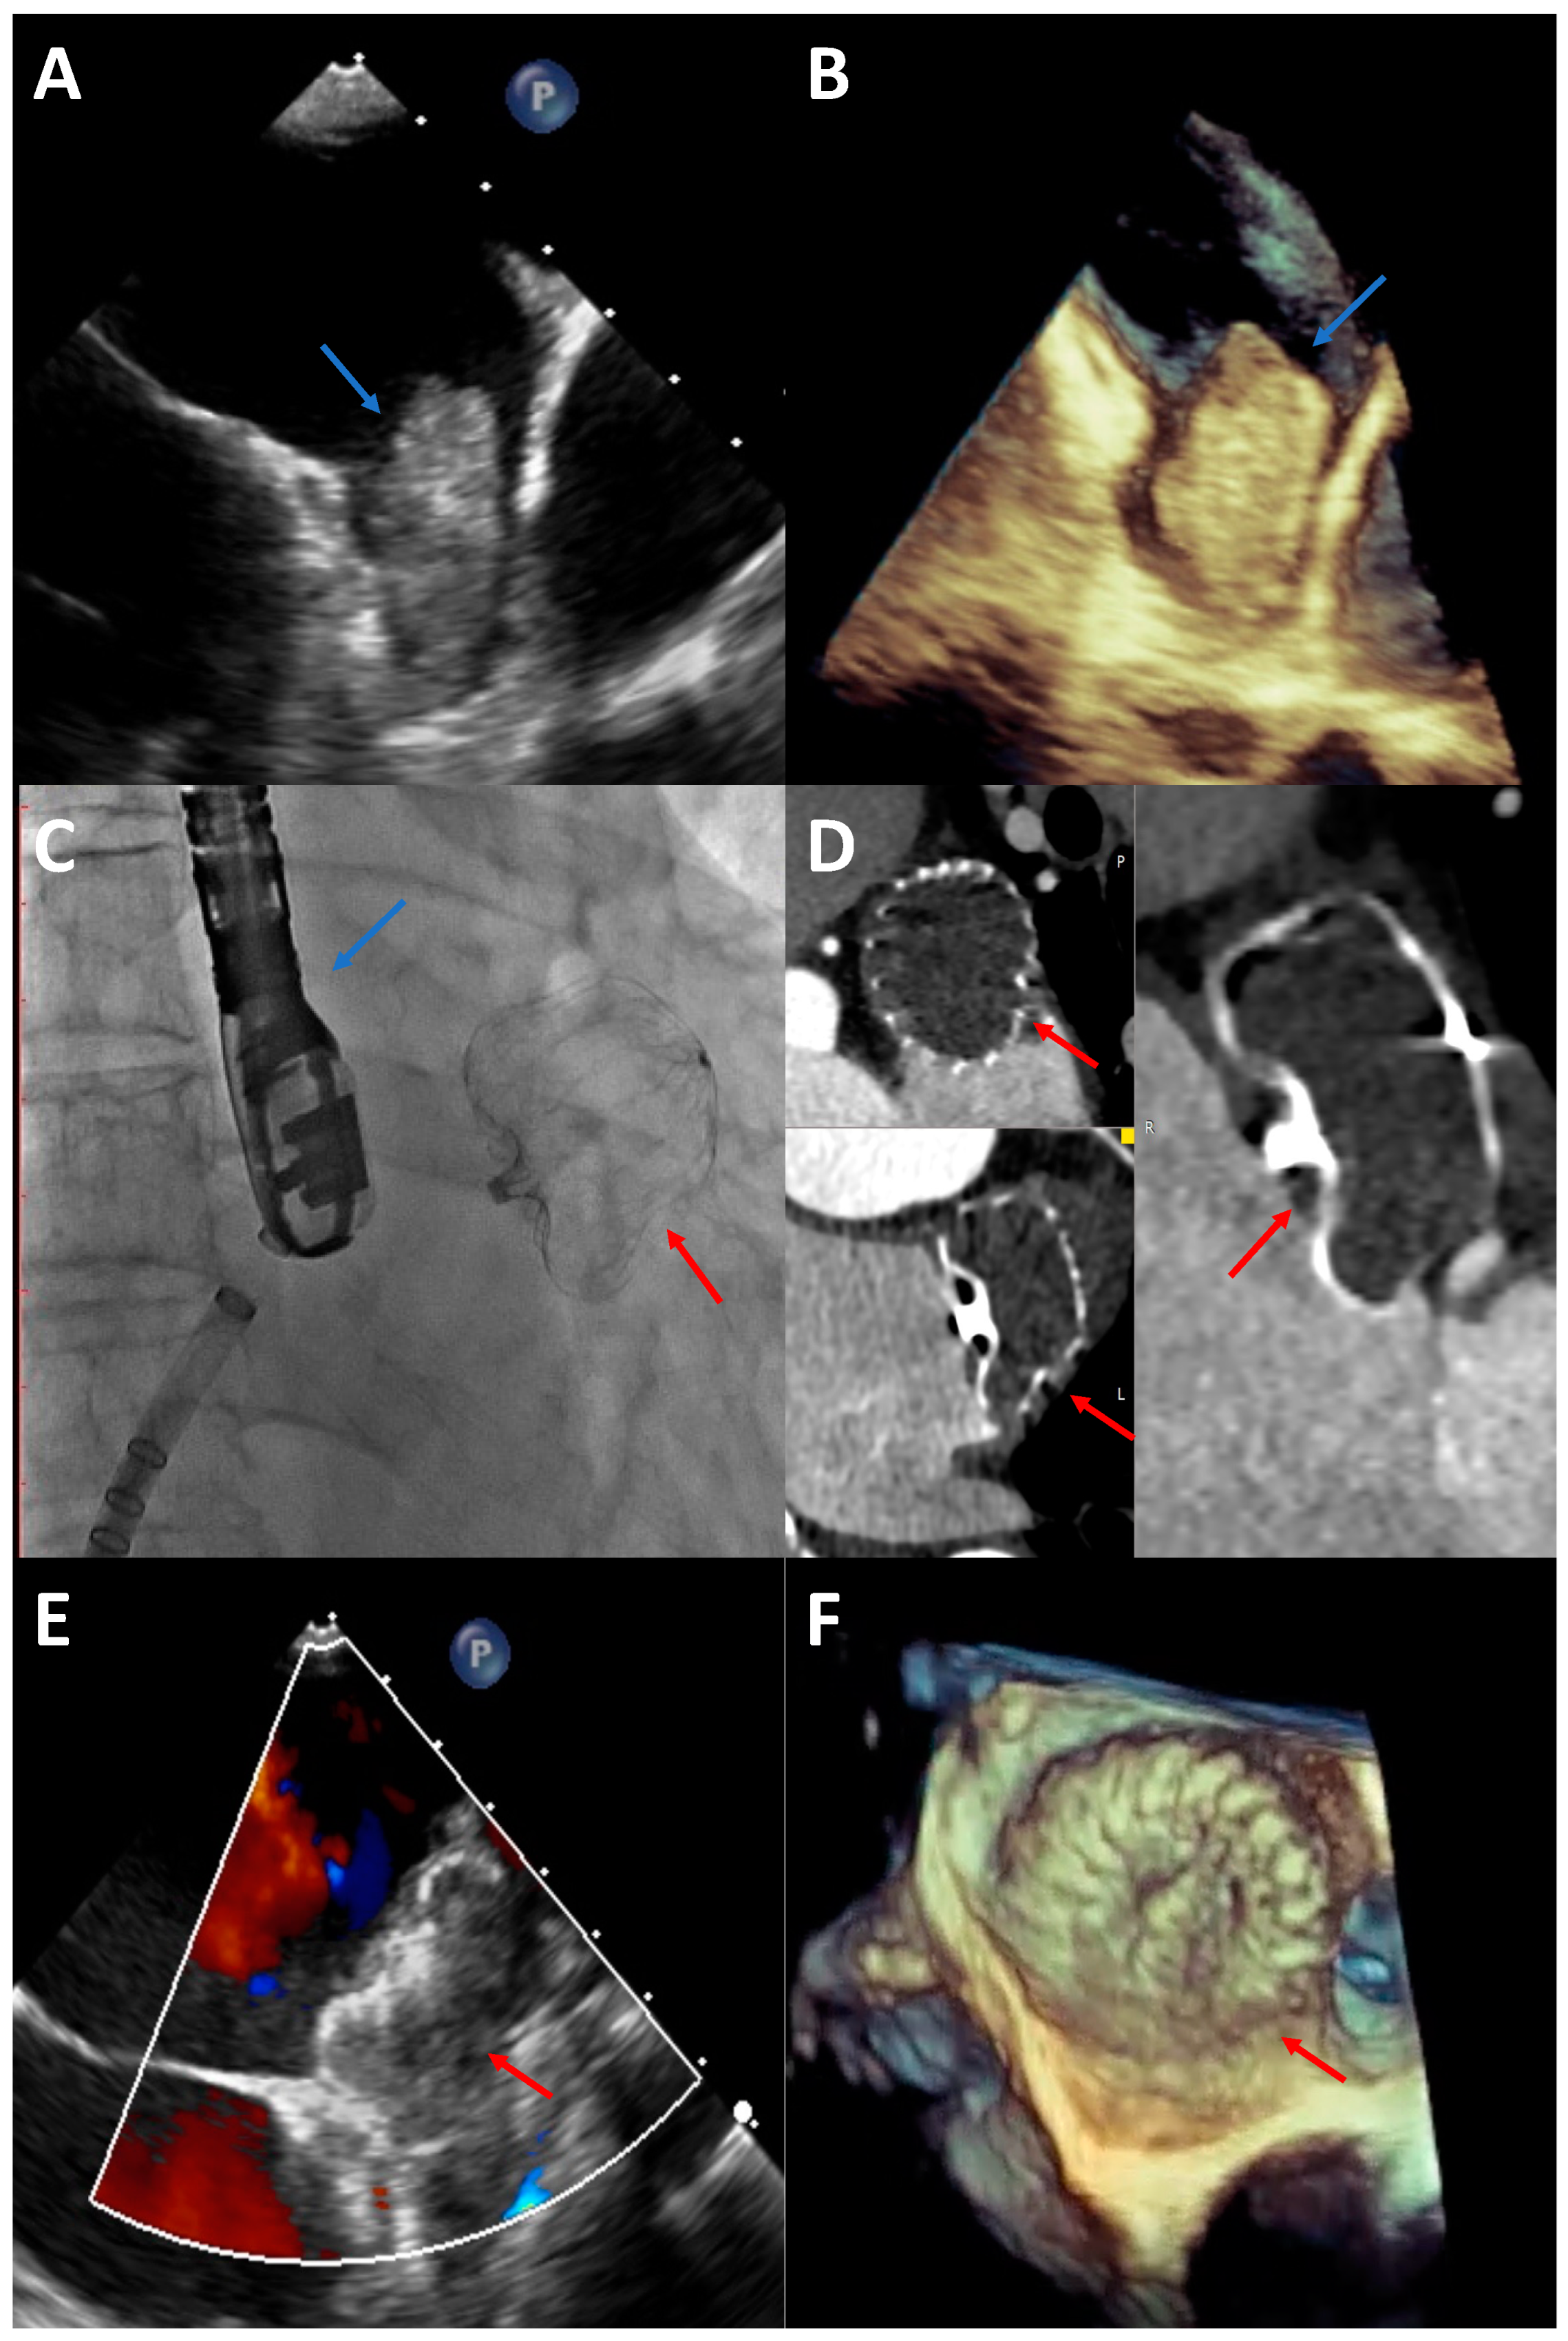

6.1. TOE

6.2. Digital Subtraction Angiography (DSA)

6.4. CCT